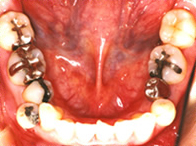

保険適用外の素材

術前![]()

術後